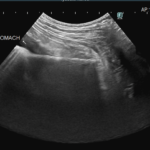

1週間前に団子を串ごと誤飲した可能性があるワンコが急にぐったりしているとのこと。すぐに地元の救急病院を受診すると異物による胃穿孔が疑われました。外科的な摘出と腹膜炎によるクリティカルケアが予想されたため紹介来院しました。開腹後、竹串による胃穿孔が確定されました。腹膜炎も同時に起こっています。穿孔創を封鎖し、腹腔洗浄とドレインの設置を行いました。幸いにも48時間後に食欲が出て退院となりました。愛犬が竹串を誤飲してしまったら、命に関わる事態に発展する可能性もあるため、早めに内視鏡による摘出をお勧めします。このような異物を発見するためにはエックス線よりも超音波検査が非常に有効です。